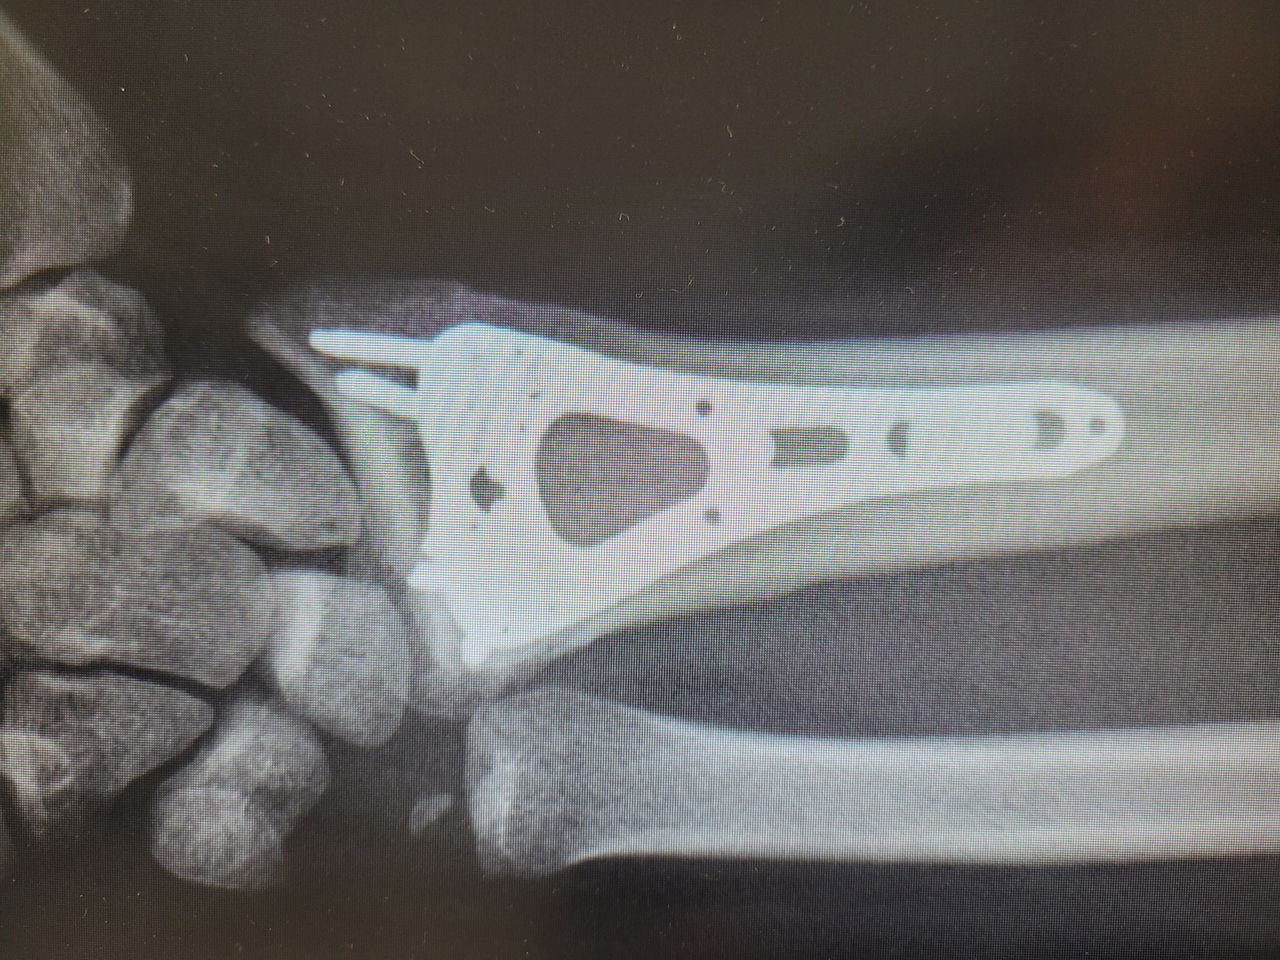

Endoprotezy stawów ręki ( kciuk, paliczki, nadgarstek ).

Zdjęcia i filmy